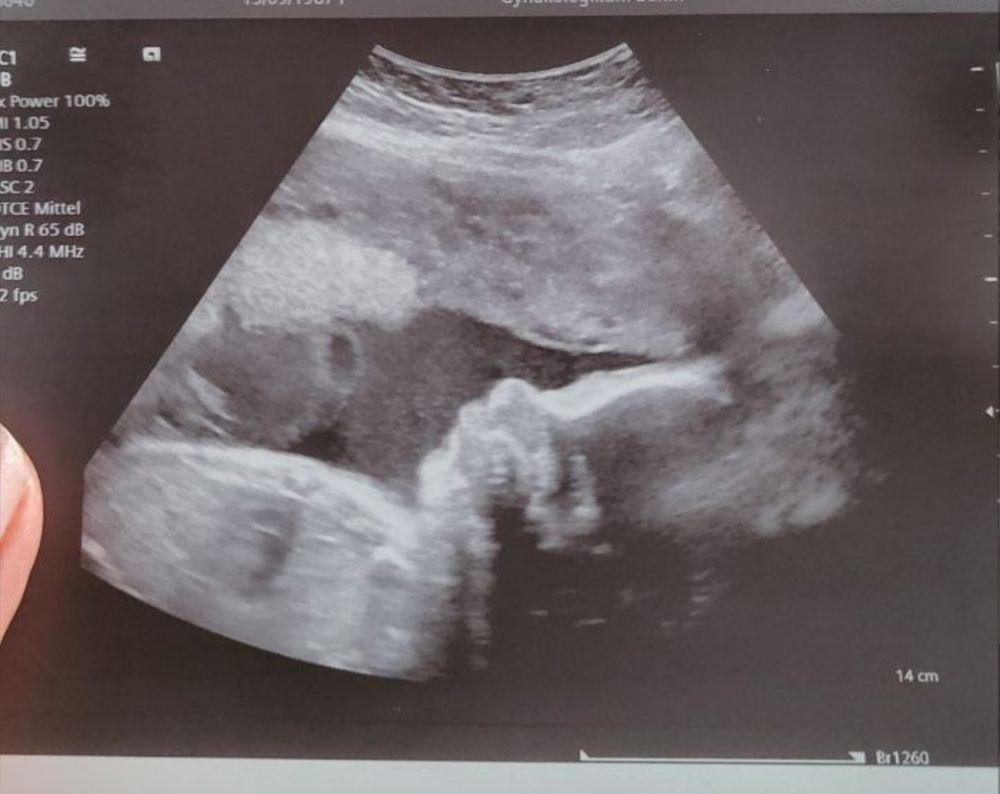

Посмотрела шейку, мои выделения, малышку и все хорошо) Вес малышки 1270 гр. Как то мне кажется маловато то. Я родилась 4100, муж 4200. Да и сами мы с мужем не маленькие. Я 175 см, муж 180 см. У нас наверно модель будет)

Фото с узи на память) До сих пор иногда не верится, что во мне растёт человечек